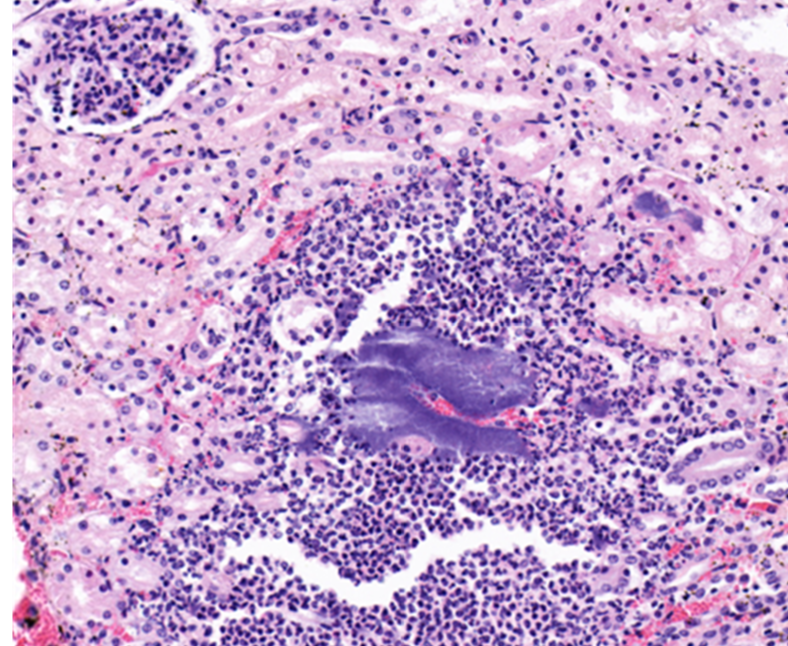

What are these cells and what does this imply about the duration?

neutrophils which suggests acute inflammation

There are bacterial colonies trapped and proliferating within the capillaries, are they post mortem or are they important in the pathogenesis of the lesions?

they are likely antemortem bacteria because they are surrounded by an inflammatory response

What would the morphologic diagnosis for this lesion?

acute purulent glomerulonephritis with bacterial colonies

Identify this structure:

bacterial colonies